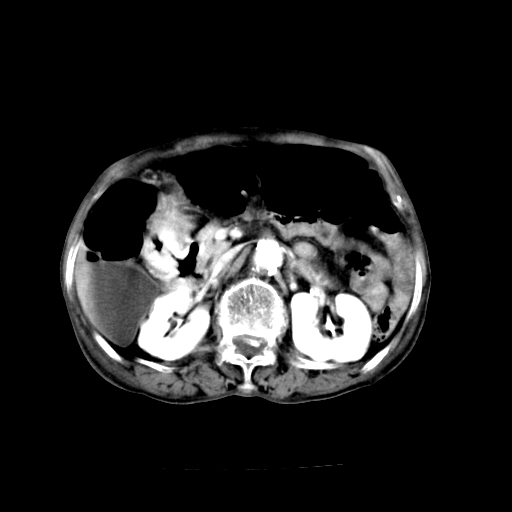

标题: CT19149:女,68岁,腹胀、恶心两周。 [打印本页]

女,68岁,腹胀、恶心两周,先做ct平扫,当时家属不同意强化,6天后家属要求增强扫描。

1、胃窦癌; 2、局灶性脂肪肝。

1)胃窦壁厚,考虑胃窦癌?建议行胃镜检查。 2)局灶性脂肪肝。